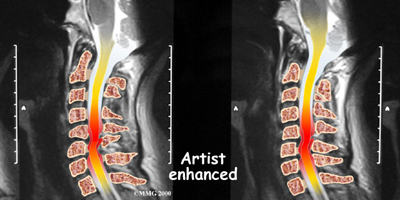

When the head and neck are suddenly and forcefully whipped forward and back, mechanical forces place excessive stress on the cervical spine. Traumatic disc rupture and soft tissue damage can occur. The cartilage between the disc and the vertebral bone is often cracked. This is known as a rim lesion.

Damage to the disc can put pressure on the nerves as they exit the spine. The pressure or irritation can be felt as numbness on the skin, weakness in the muscles, or pain along the path of the nerve. Most people think of these symptoms as indications of a pinched nerve. Health care providers call this condition cervical radiculopathy.

If more information is needed, your doctor may order an MRI. The MRI machine uses magnetic waves rather than x-rays to create pictures of the cervical spine in slices. MRIs show the cervical spine vertebrae, as well as the soft tissue structures, such as the discs, joints, and nerves. MRI scans are painless and don't require needles or dye. MRI scan has become the most common test to look at the cervical spine after x-rays have been taken.